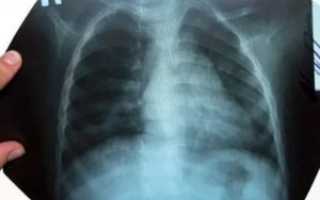

Крупозная пневмония на рентгенограмме прослеживается, как крупное среднеинтенсивное затемнение. Оно проецируется на одну или обе легочные доли. Болезнь провоцируется палочкой Фриндлера и относится к ряду тяжелых жизне угрожающих заболеваний.